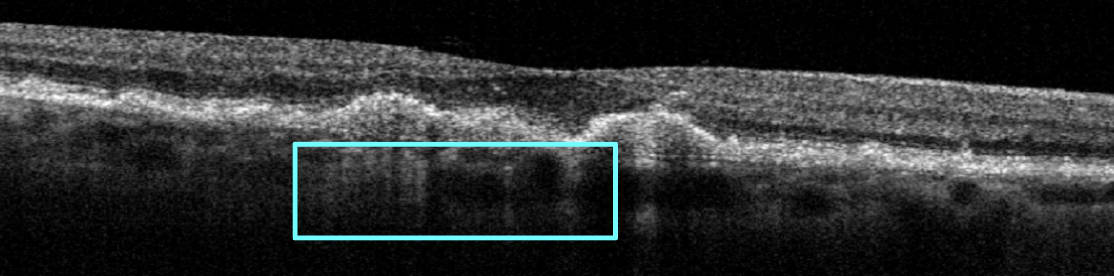

Complete RPE and outer retina atrophy (cRORA) is defined by CAM as a 250 μm continuous hypertransmission zone with overlying atrophy of the photoreceptor and RPE layers (see Figure 4)—a state that meets the clinical definition of GA. This stage is significant because it aligns with studies that have evaluated complement cascade inhibition therapy for GA treatment. Because cRORA is the stage targeted by these clinical trials, identifying it promptly is essential for discussions on treatment options.